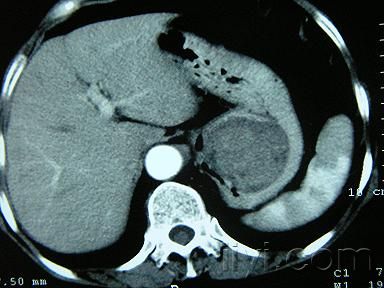

術前通常難以確診。胃鏡檢查可見隆起于胃黏膜下的半球形腫塊。胃腸氣鋇造影可見邊緣規(guī)則的充盈缺損,腫瘤表面胃黏膜光滑。B超和CT檢查多可確定腫瘤的位置、大小以及與周圍臟器的關系。